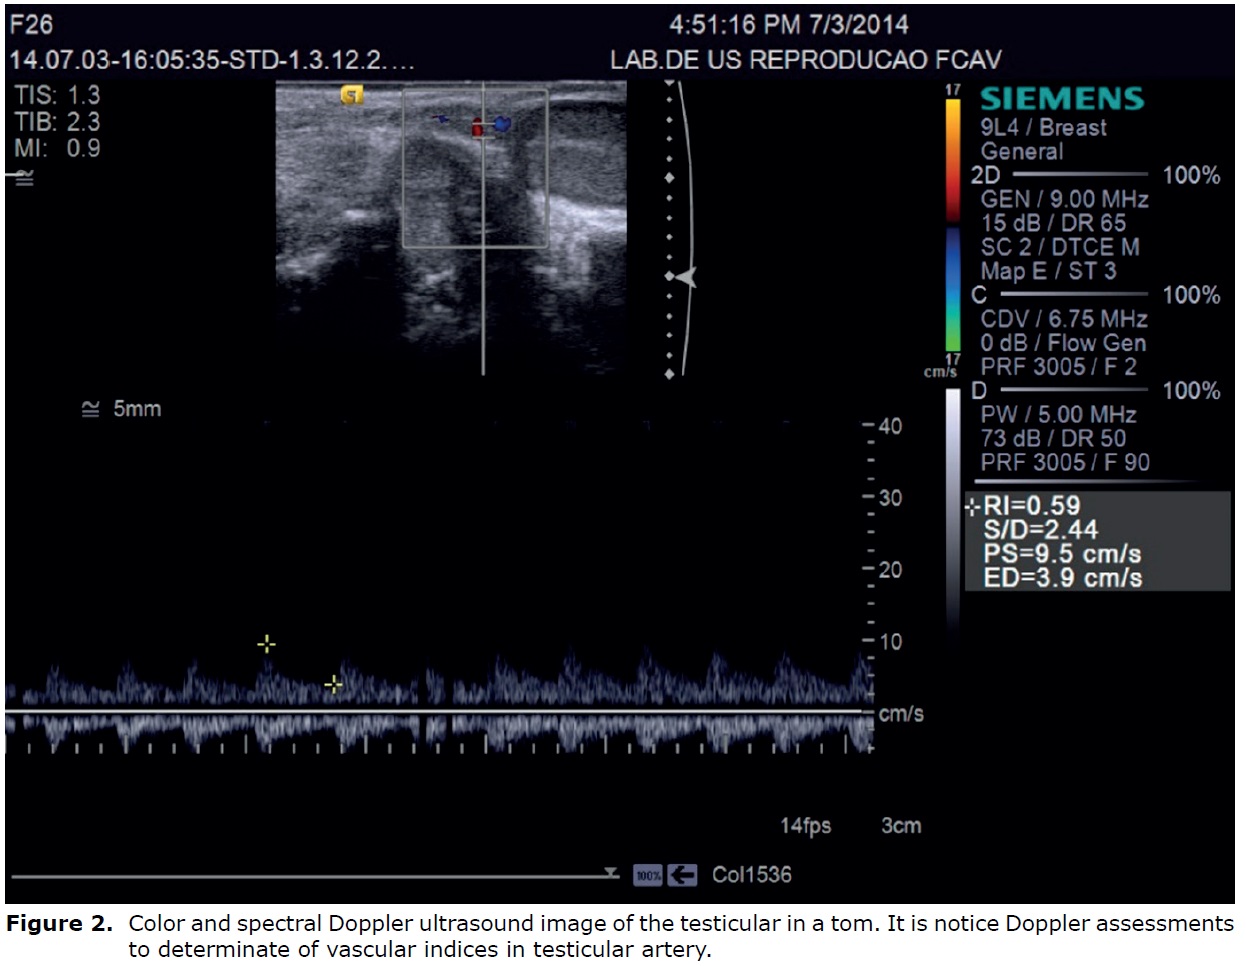

Using the color Doppler, the detection of feline testicular artery are consistent, identified dorsally, between testicular, epididymal structures, and tortuous pattern. However, the identification of marginal and intratesticular portions of the testicular artery in cats are limited, probably due to the small testicular volume (7).

The main characteristics evaluated by Doppler mode are calculate vascular indices: peak systolic velocity (SV), end-diastolic velocity (DV) and resistance index (RI = [PSV - DV] / SV). These also present the advantage, compared to measurement of flow velocity, of being independent of insonation angle (3,24).

In cats, the spectral Doppler, the testicular artery showed characteristics waves of low resistivity, with low pulsatility and resistance, featuring flows with large and continuous systolic peaks and high-speed flow during diastole, typical of organs with continuous demand for blood. Regarding the vascular indices of the testicular artery in cats, the values for systolic and diastolic velocities and resistance index are (Left testicle SV: 6.73±2.78 and DV: 2.80 ± 1.50 cm/s and RI: 0.54 ± 0.12; Right testicle SV: 6.23 ± 2.34 and DV: 2.77 ± 1.36 and RI: 0.53 ± 0.12). As this feature depends on other factors such as vessel diameter and blood flow region, with no influence of the tissue evaluated size (7) (Figure 2).